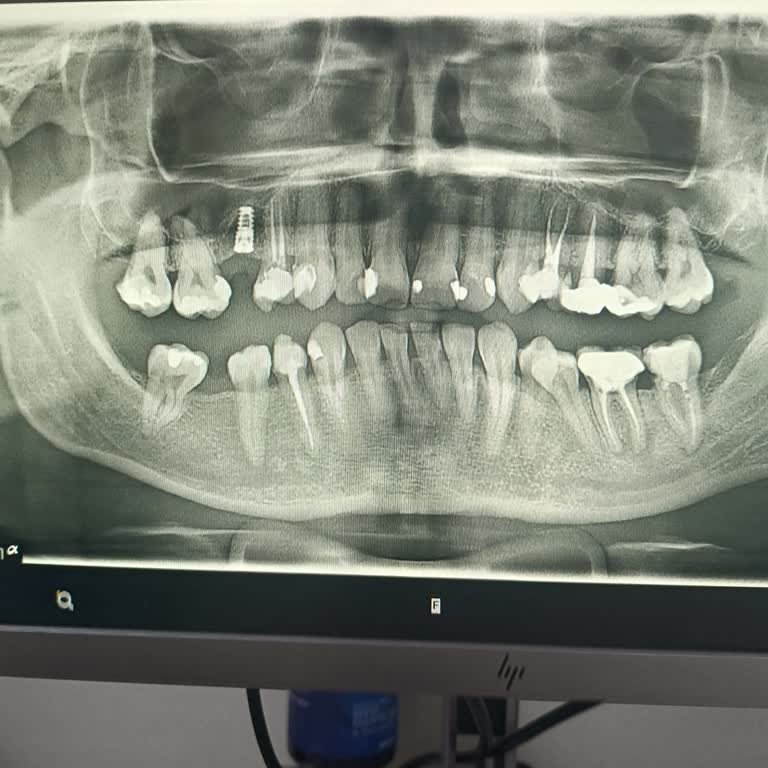

2022 Ocak ayında İstanbul Bağcılar Erkut Ağız ve Diş Sağlığı Merkezi’nde E***** E*** tarafından gerçekleştirilen implant işlemi sırasında, işlem öncesi ve sonrası röntgen çekilmeden uygulama yapıldı. Bu nedenle implant yanlış yerleştirildi ve sinir hasarı oluştu. İşlem için IBAN üzerinden 4.000 TL ö...